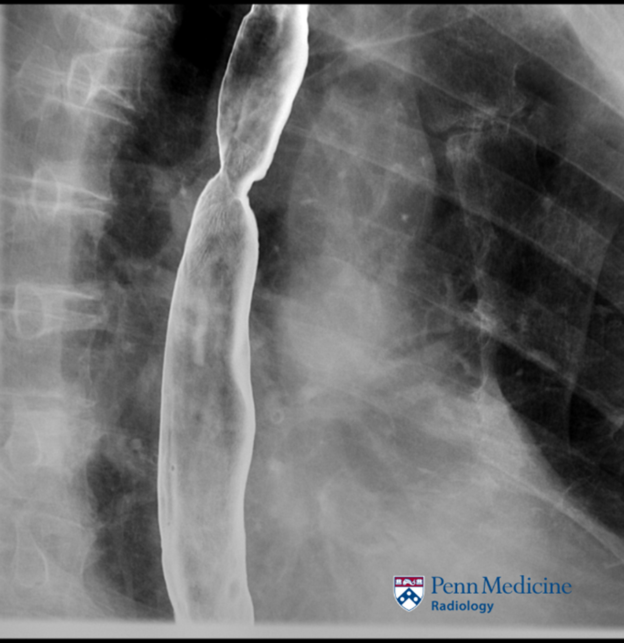

64-year-old man with dysphagia and rapid weight loss

A 64-year-old man with a past medical history of alcohol and tobacco use, rheumatoid arthritis, hyperlipidemia, and hypertension, presented with dysphagia and 20-pound weight loss over two to three months.